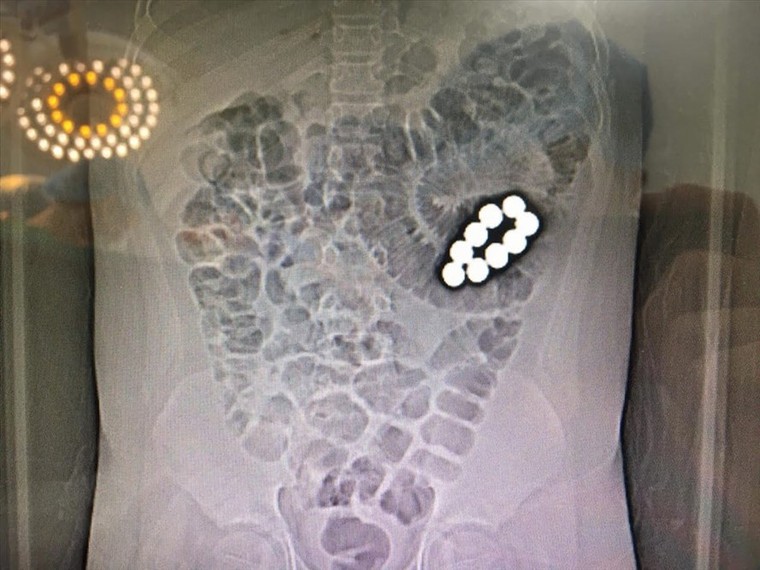

Về sự việc trên, chiều 24.9 thông tin từ BV Quận Thủ Đức cho biết, sáng 22.9, bệnh nhi L. được người nhà đưa đến Khoa Cấp cứu BV quận Thủ Đức do đau bụng nhiều, bụng chướng và nôn ói. Sau khi khám, chụp Xquang, siêu âm và CT MRI…, các bác sĩ chẩn đoán bệnh nhi bị tắc ruột do dị vật, cần chuyển mổ cấp cứu gấp.

Trong khi tiến hành can thiệp mổ, bác sĩ phát hiện bệnh nhân bị tắc ruột do 9 viên bi nam châm bằng sắt nằm ở 2 khoang ruột khác nhau. Một khoang chứa 7 viên và khoang còn lại chứa 2 viên. Hai nhóm viên bi bị nam châm hút 2 đoạn ruột lại với nhau gây tắc ruột hoàn toàn và gây hoại tử ruột.

Các bác sĩ BV quận Thủ Đức phải tiến hành cắt một đoạn ruột để lấy 9 viên bi ra, loại bỏ phần ruột bị hoạt tử và khâu nối lại ruột. Sau 3 giờ căng thẳng, ca phẫu thuật đã thành công tốt đẹp.